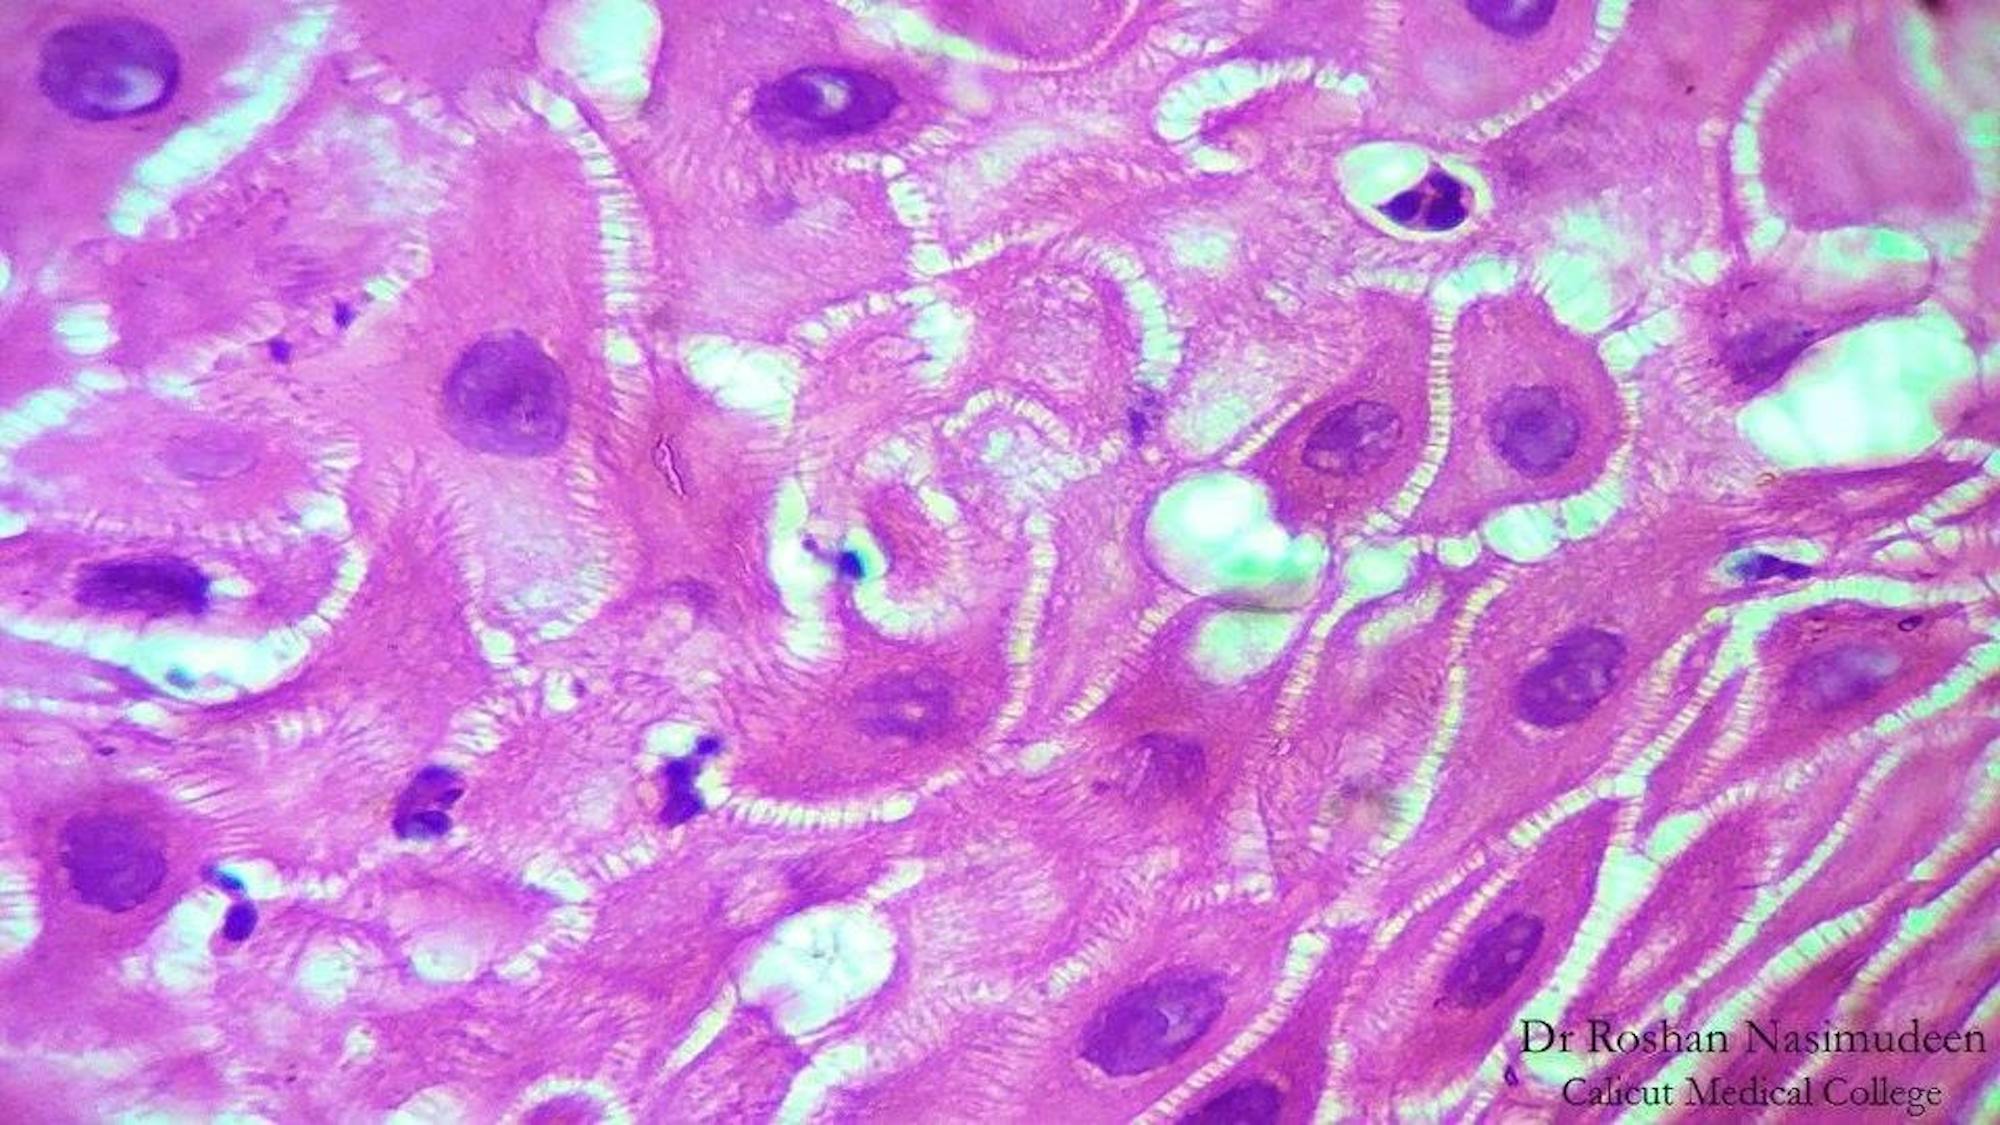

Researchers used a voltage sensitive dye — Berkeley Red Sensor of Transmembrane Potential — to compare young, actively dividing cells with cells that had remained in culture for 50 days.

In young cells, the researchers observed distinct clusters formed metaphorical neighborhoods where cells could coordinate behavior. This diversity and “neighborhood” separation is lost as cells become senescent. This discovery suggests that bioelectric patterns in tissues and organs direct their own morphology, important for the development of human anatomy and anatomical function.